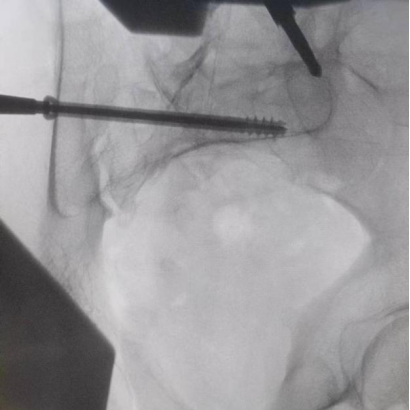

圖為吳宏華主任術中于健側髂后上級置入信號收集裝置

圖為透視下見置入的骶髂螺釘,位置、長度精準,無絲毫偏差